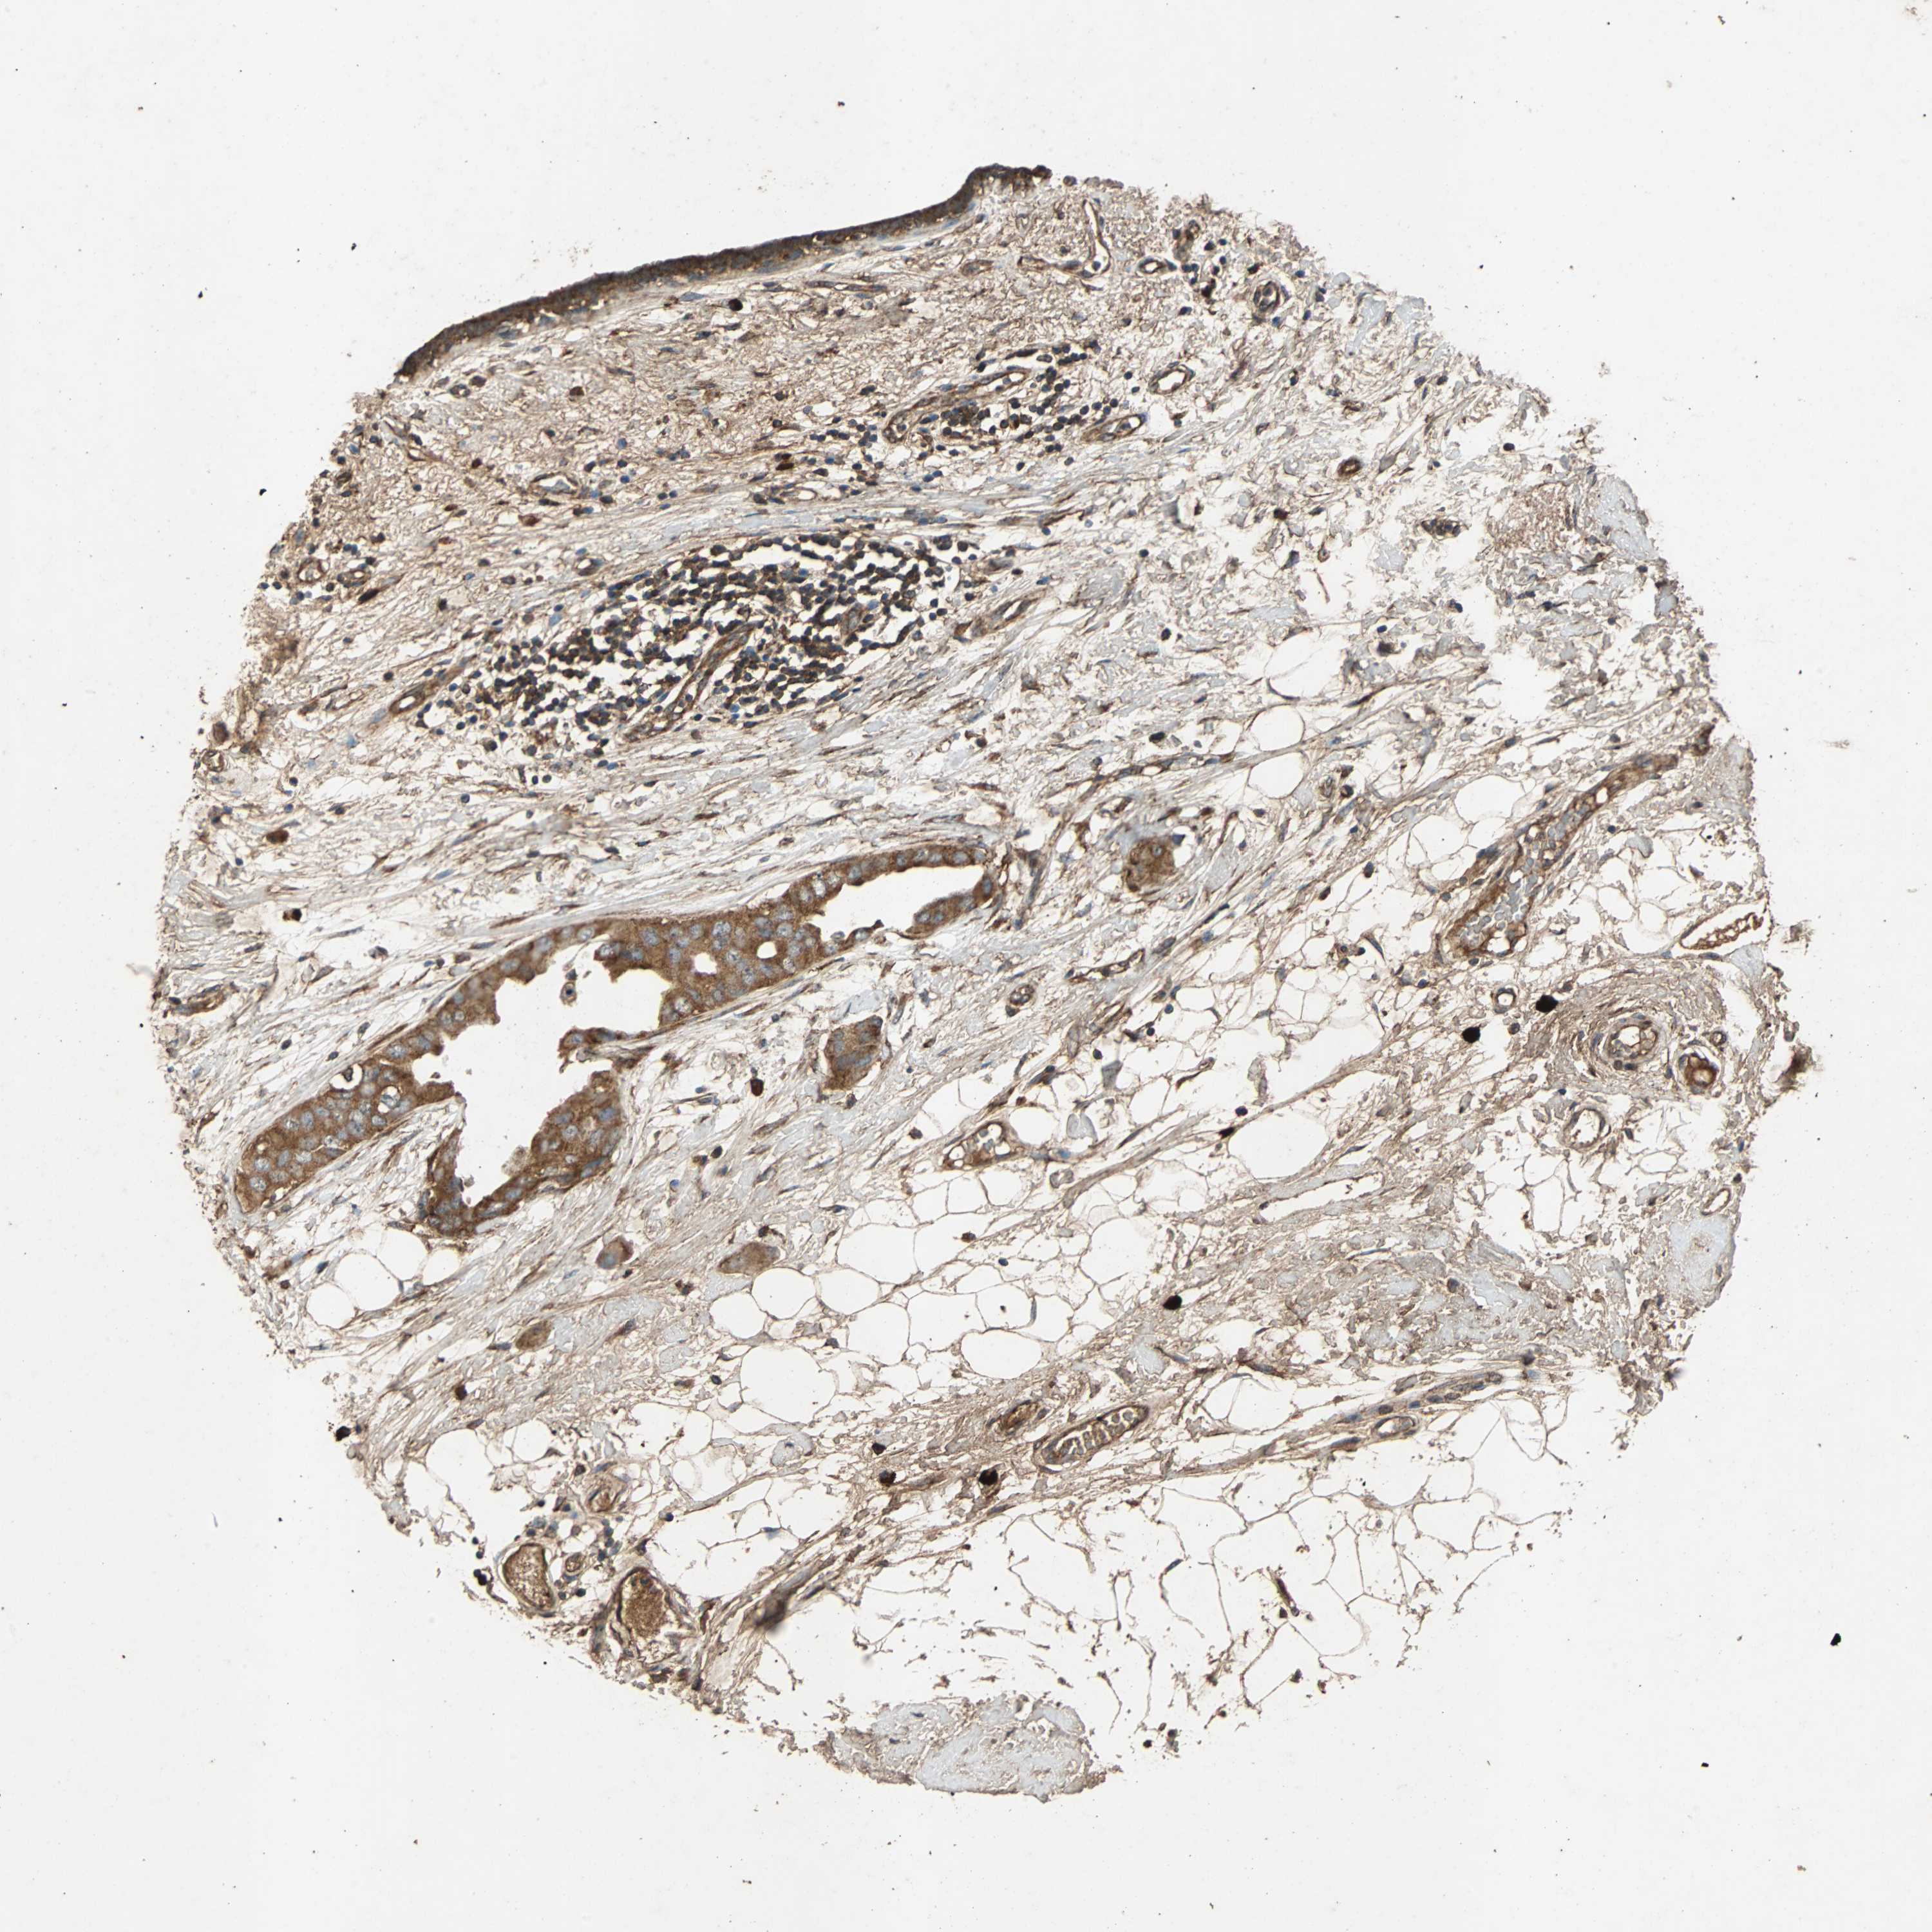

CANCER BREAST CANCER Show tissue menu

BRCA TCGA BRCA VALIDATION PROTEIN EXPRESSION

Breast cancer

Human cancer